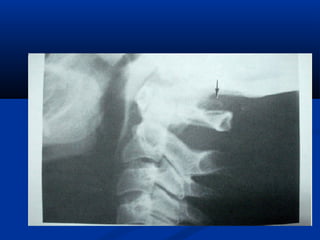

In anterior arch rachischisis, the anterior arch appears fat or

plump and rounded in configuration, appearing to ‘‘overlap’‘

the odontoid process

(making identification of

the predental space impossible);

the arch may have unsharp,

duplicated anterior margins